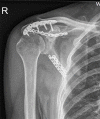

Fracture of the scapular neck combined with rotator cuff tear: A case report

Case summary: A 62-year-old man was admitted to our emergency department 6 h after his right shoulder and back were impacted by heavy objects. The patient presented chest tightness and shortness of breath. Chest computed tomography (CT) showed pneumohemothorax, multiple rib fractures, and right scapula fractures. Three-dimensional CT reconstruction of the right shoulder joint showed a trans-spinous scapular neck fracture with a glenohumeral joint dislocation. Rotator cuff injury was suspected because the patient had a glenohumeral joint dislocation and was then confirmed by shoulder magnetic resonance imaging. A staged surgery was performed, including open reduction and internal fixation of the right scapula fracture and repairing of rotator cuff by right shoulder arthroscopy. At the 5-mo follow-up, the fracture line was blurred and the shoulder joint function was good.